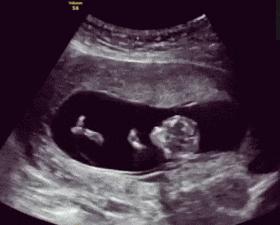

相关数据分析,常见的胎动每小时不少于3-5次,如果平均每小时胎动超过10次,孕妈就要考虑胎动是否过于频繁了。

孕晚期胎动频繁,胎动次数大于等于30次/12小时,或大于等于4次/小时,都是正常的范围,孕妈们不必过于担心。

孕妈在怀孕晚期,应该去自主数胎动次数,可以根据胎动次数来判断。

宝宝目前是否健康,胎动最低的次数为10次每天,常见的次数最多30到40次。

如果在出现胎动比较频繁时,甚至超过以上这些次数,孕妈需要和家人去医院进一步检查,避免出现什么异常,有问题建议宝妈们及时去解决。